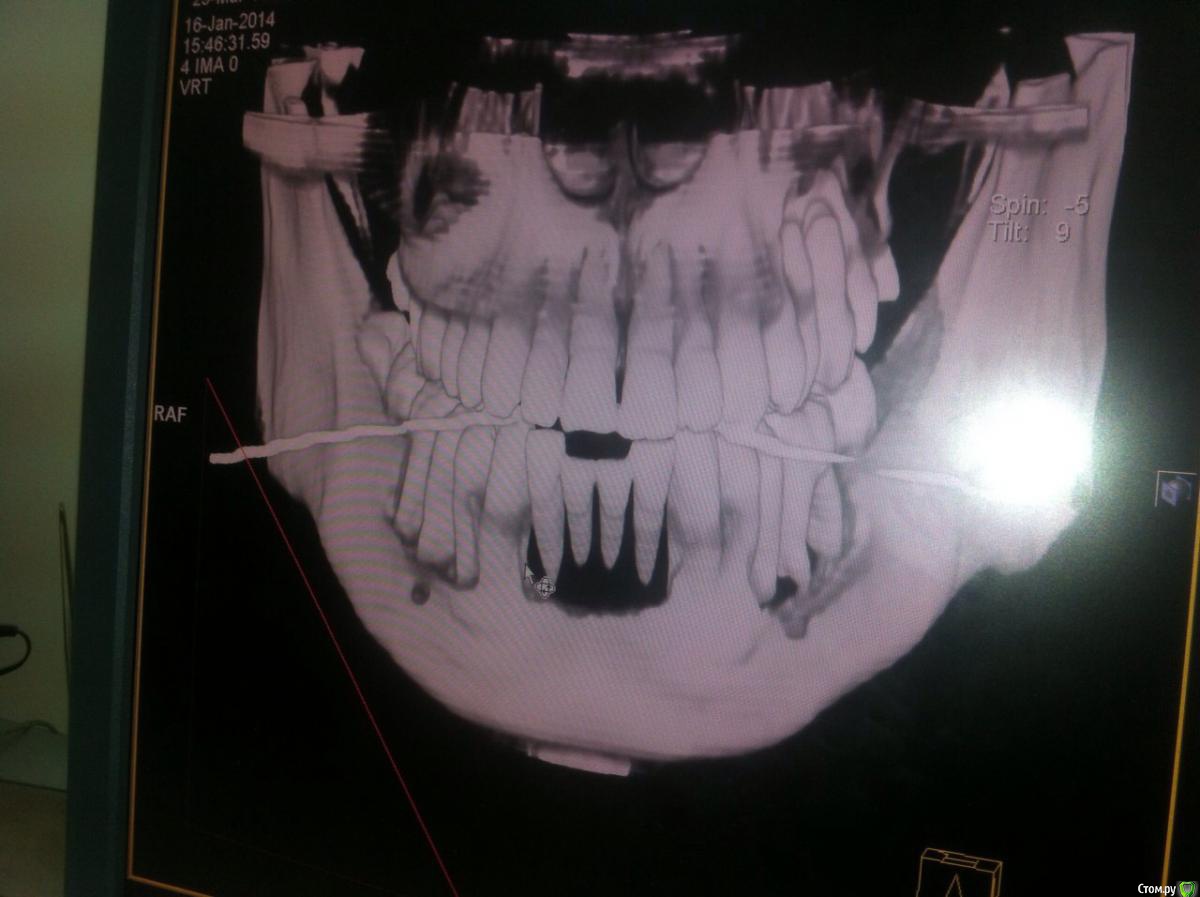

9148553387t Опубликовано 23 апреля, 2015 Поделиться Опубликовано 23 апреля, 2015 Подскажите,что это??на сегодняшний день,еще больше зубов стали опускаться вниз. Ссылка на комментарий

9148553387t Опубликовано 23 апреля, 2015 Автор Поделиться Опубликовано 23 апреля, 2015 Давайте всю Ктк сожалению,это единственный снимок,снимок не мой,а брата,этот был сделал 1,5 года назад,на сегодняшний день ,стали опускаться и клыки тоже,снимки у врача,врачи ничего не могут сказать. Ссылка на комментарий